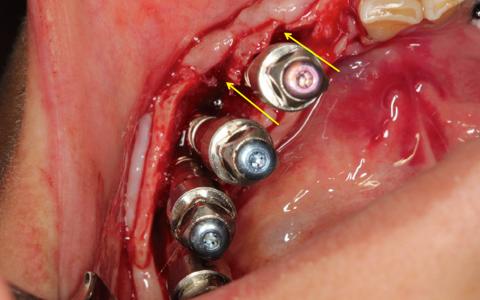

Paciente de 36 años al que le extrajeron los dientes del 3 cuadrante aproximadamente hace 16 años, se observa una cresta de 2mm con un tejido óseo irregular. Se decide hacer una prótesis híbrida con 6 implantes realizando primero una expansión con colocación de implantes en el mismo acto quirúrgico, en las dos hemiarcadas.

Plan de tratamiento: Expansión en casos extremos para recuperar la dimensión transversal. Complicación.